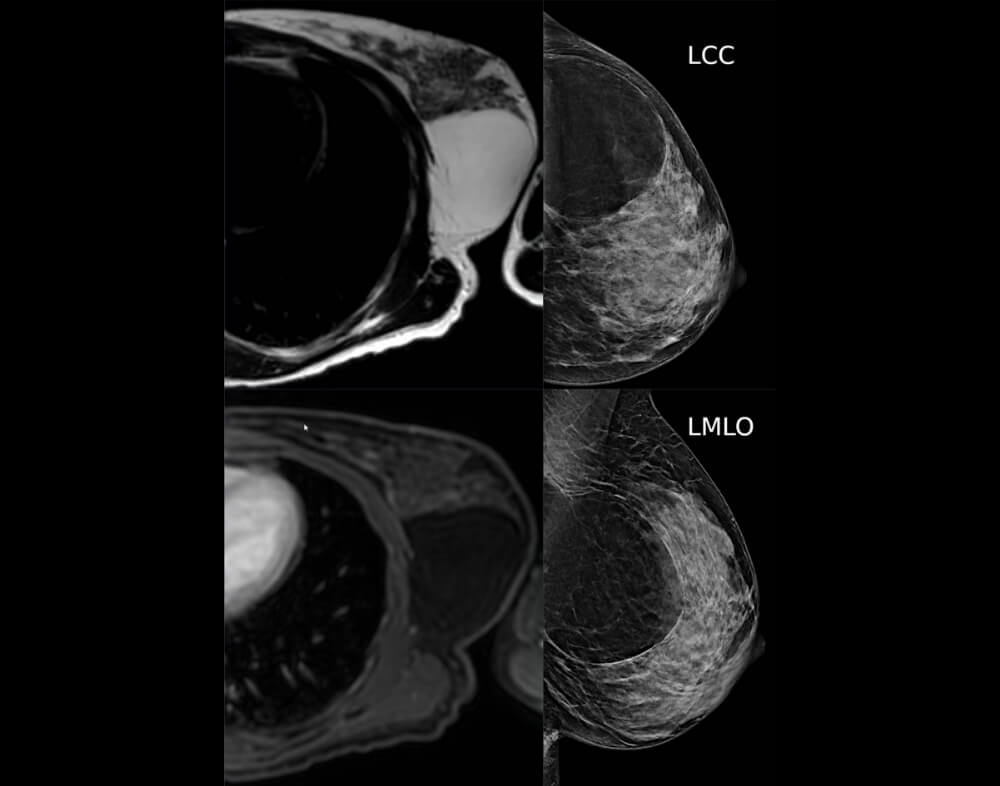

Το λίπωμα είναι καλοήθη όγκος.

Αποτελείται από λιπώδη ιστό (λίπος) και συνήθως εντοπίζεται επιφανειακά στο υποδόριο λίπος.

Στο υπερηχογράφημα μπορεί να υπάρχουν ευρήματα ενδεικτικά καλοήθους βλάβης.